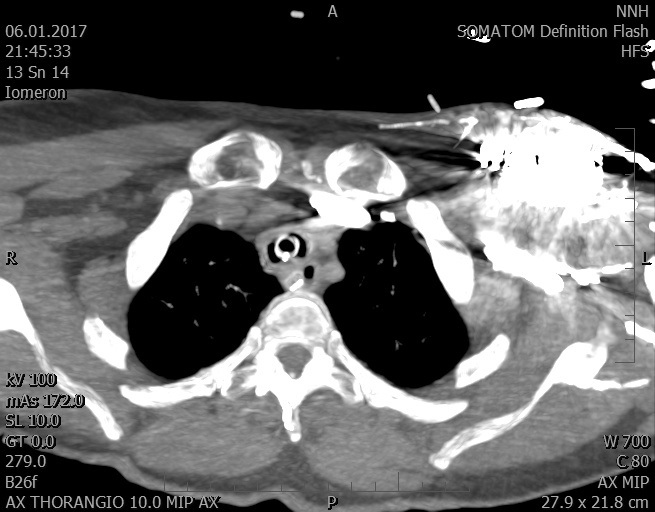

Video 2 - Echokardiograficky byla zjištěna těžká dysfunkce dilatační levé komory s nezvětšenou pravou komorou.Pro nejasnou příčinu zástavy jsme provedli i vyšetření výpočetní tomografií (CT), které vyloučilo plicní embolizaci (série 1 - soubory na konci článku). V den přijetí při přetrvávající oběhové nestabilitě byla nemocná opakovaně defibrilována pro fibrilaci komor se stabilizací rytmu po podání amiodaronu a mesocainu. Dle hemodynamických měření se jednalo o těžký kombinovaný šok. Vstupní laboratorní vyšetření bylo bez větších pozoruhodností. Posléze jsme doplnili anamnézu od příbuzných a zjistili, že pacientka užila do dvou hodin před srdeční zástavou první tabletu amoxicilinu na lehký respirační infekt. Při nevýtěžnosti vstupních vyšetření a nových anamnestických informacích jsme doplnili 14 hodin po kolapsu vyšetření koncentrace tryptázy v séru, která byla extrémně zvýšena (tabulka 2), což nás vedlo k podezření na anafylaxi.